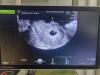

Во вторник записалась на узи будет 6.2 надеюсь все хорошо и увидят сердечко с сыном на этом сроке уже было, вечером в жк на прием.

Ходила ровно в 6 недель, только-только забилось на узи🥺 107 чсс

стикер